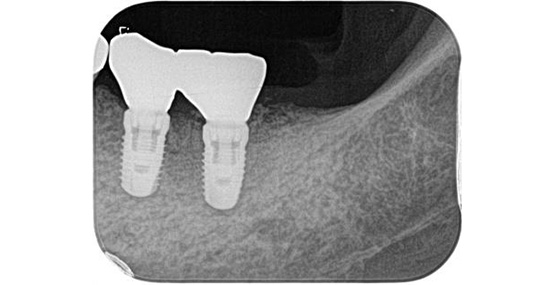

一次手術後(インプラント体埋入後の写真です)

インプラント手術後は大きなトラブルもなく、現在はしっかり咬めて違和感がない状態で経過しています。

インプラントの植立位置を工夫することによって左下の被せものの厚みが確保され、被せものが割れにくい構造にすることができました。

術前の被せものの厚みが薄いという問題点も骨の高さ及びインプラント体を入れる深さを調整することにより十分な被せものの厚みが確保できています。